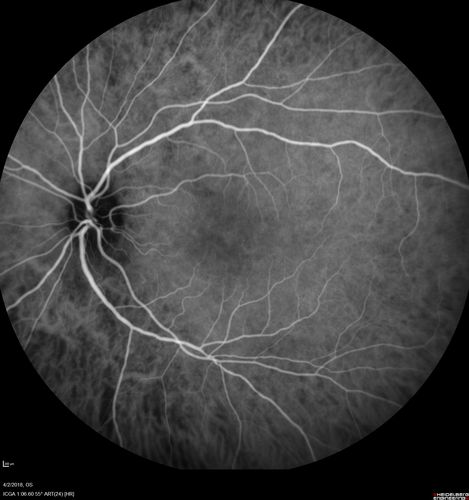

Cat Scratch - Neuroretinitis OD AND retinitis OS - Bartonella henselae positive

27 year old female with exposure to cats and prior fever.  Reports with recent vision loss right eye.  She was treated with doxycycline and within 2 weeks the right eye looks better.  Then she skipped all follow-up visits.  The right eye presented 20/200 and the left 20/16